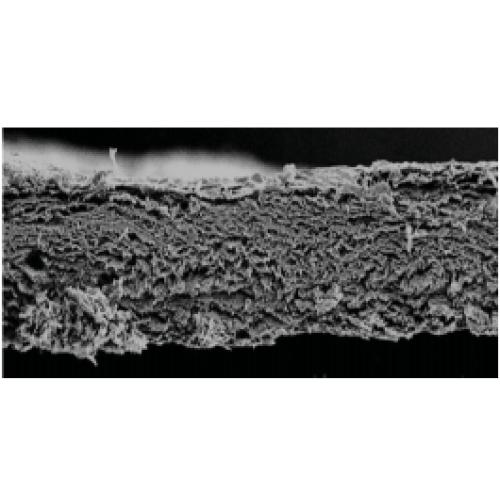

MatrixFlex™ regenerative collagen dental membrane is a strong, conformable collagen barrier membrane manufactured from purified porcine peritoneum tissue. It is intended for us in oral surgical procedures as a resorbable membrane material for guided bone regeneration procedures, augmentation around implants placed in immediate extraction or delayed extraction sockets, alveolar ridge reconstruction, filling of infrabony periodontal defects and defects after root resection, and guided tissue regeneration procedures in periodontal defects.

MatrixFlex™ is the newest membrane to be added to the membrane portfolio, designed to provide a very drapable yet very strong membrane. This combination of drapability and strength is maximized in this membrane, while maintaining a handling characteristic that allows the membrane to be repositioned if

necessary and does not stick to instruments during placement.